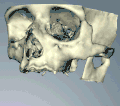

Компьютерная томография может быть загружена в программное обеспечение CAD/CAM для создания симуляции требуемой обработки. Затем устанавливаются виртуальные имплантаты и на данных 3D-принтер создаётся стент.